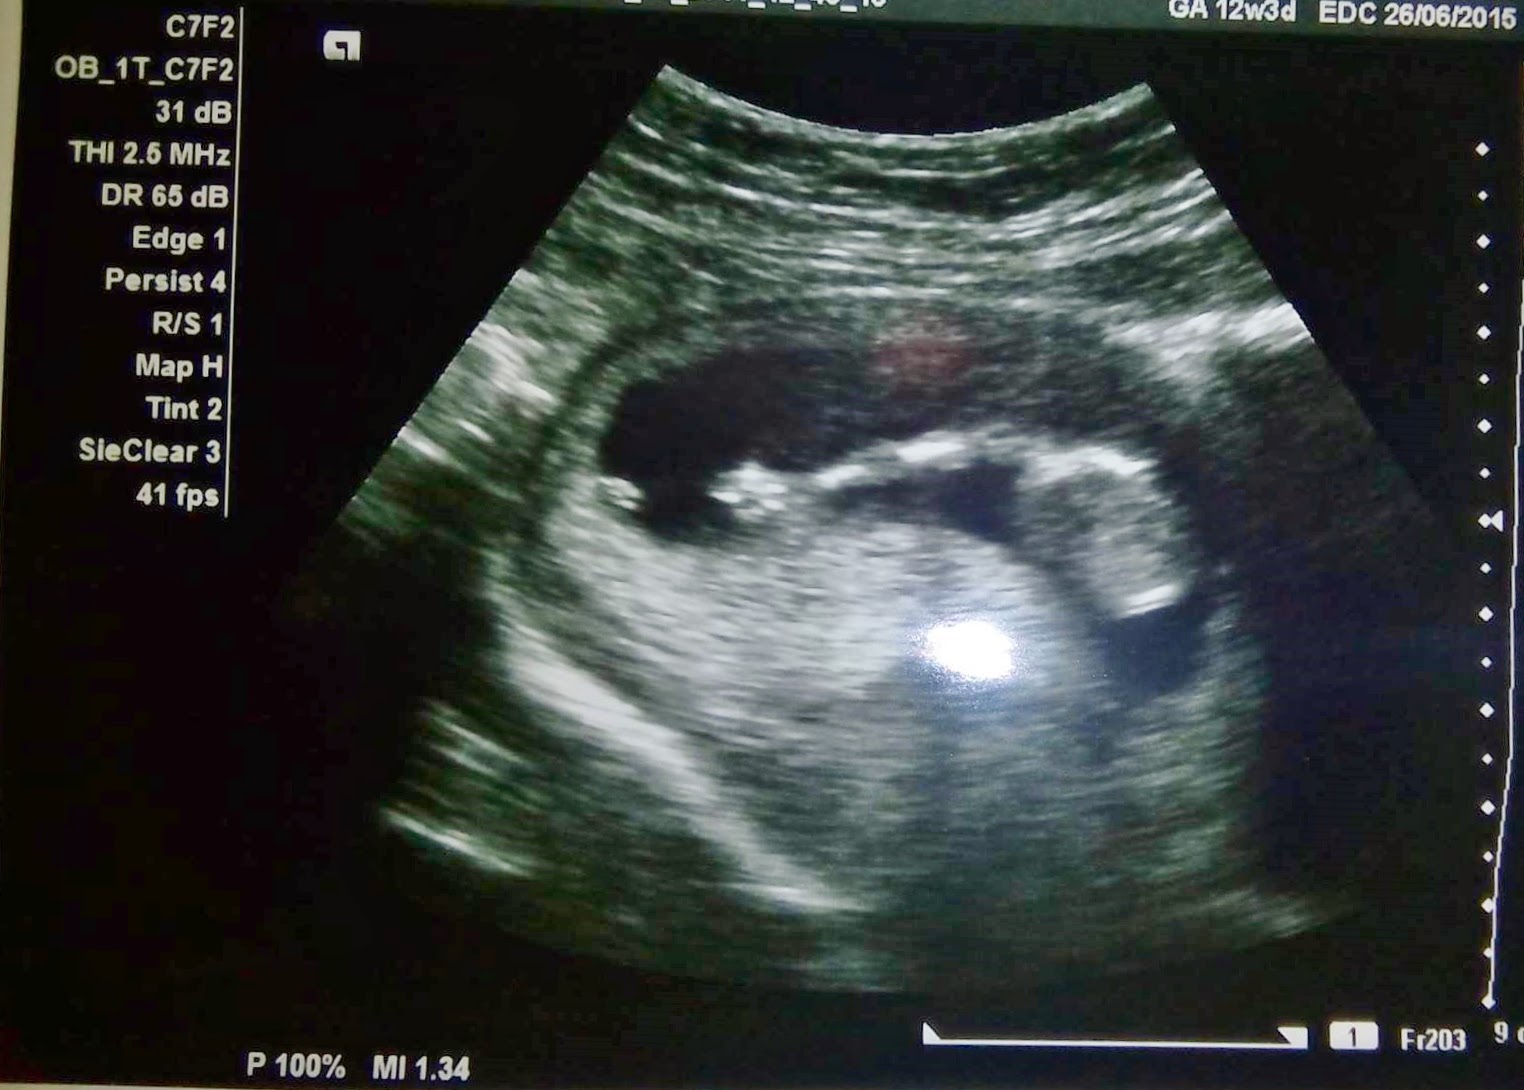

primeira ecografia

fui fazer a primeira ecografia com 13 semanas quase (sim e por pouco não passava o tempo, mas aqui nesta terra é tudo assim) e assim que a médica começou á procura do bebé ele apareceu logo... mas de costas para a minha barriga e de cabeça para baixo, tipo morceguinho. :P lá andou a médica a ver se ele se virava e tal e ele fez uma cena brutal. a médica apontou para o ecrã e disse "estão a ver isto? é o bracinho dele." e opah, dava para ver tão bem, um bracinho com uma mãozinha e dedinhos. então o scaninha abre a mão e fecha. e a médica "olha que giro, está a dizer olá aos papás!" e eu olho para o meu Fábio e está ele com um sorriso tão grande e uma cara de parvo tão engraçada que só me dava vontade de rir. "querem ouvir o coraçãozinho dele?" e aí é que fo**u tudo. quando ela põe o som alto e eu oiço aquele coraçãozinho a bater acelerado..não me consegui conter e as lágrimas começaram a escorrer-me pela cara sem eu sequer me dar conta quase. "está emocionada? :) pode chorar á vontade, é mesmo um momento emocionante." disse a médica, mas eu lá me controlei e não desatei a chorar, nem sei como porque o Fábio começou a apertar-me a mão e a olhar para mim e para o monitor com aquela cara.. ai mãe.

sabem, já tinha visto gente a chorar de emoção, em casamentos ou coisas assim, mas a mim nunca me tinha acontecido. não sei, nunca senti tanta alegria que me desse vontade de chorar. e naquele momento não sei o que senti, foi alegria, emoção, acho que foi também um bocado o cair a ficha, do estilo, "estou mesmo grávida, tenho mesmo um bebé a crescer dentro de mim, isto é mesmo real".

da direita para a esquerda pode-se ver a cabeça e depois o ombro e o braço. :)